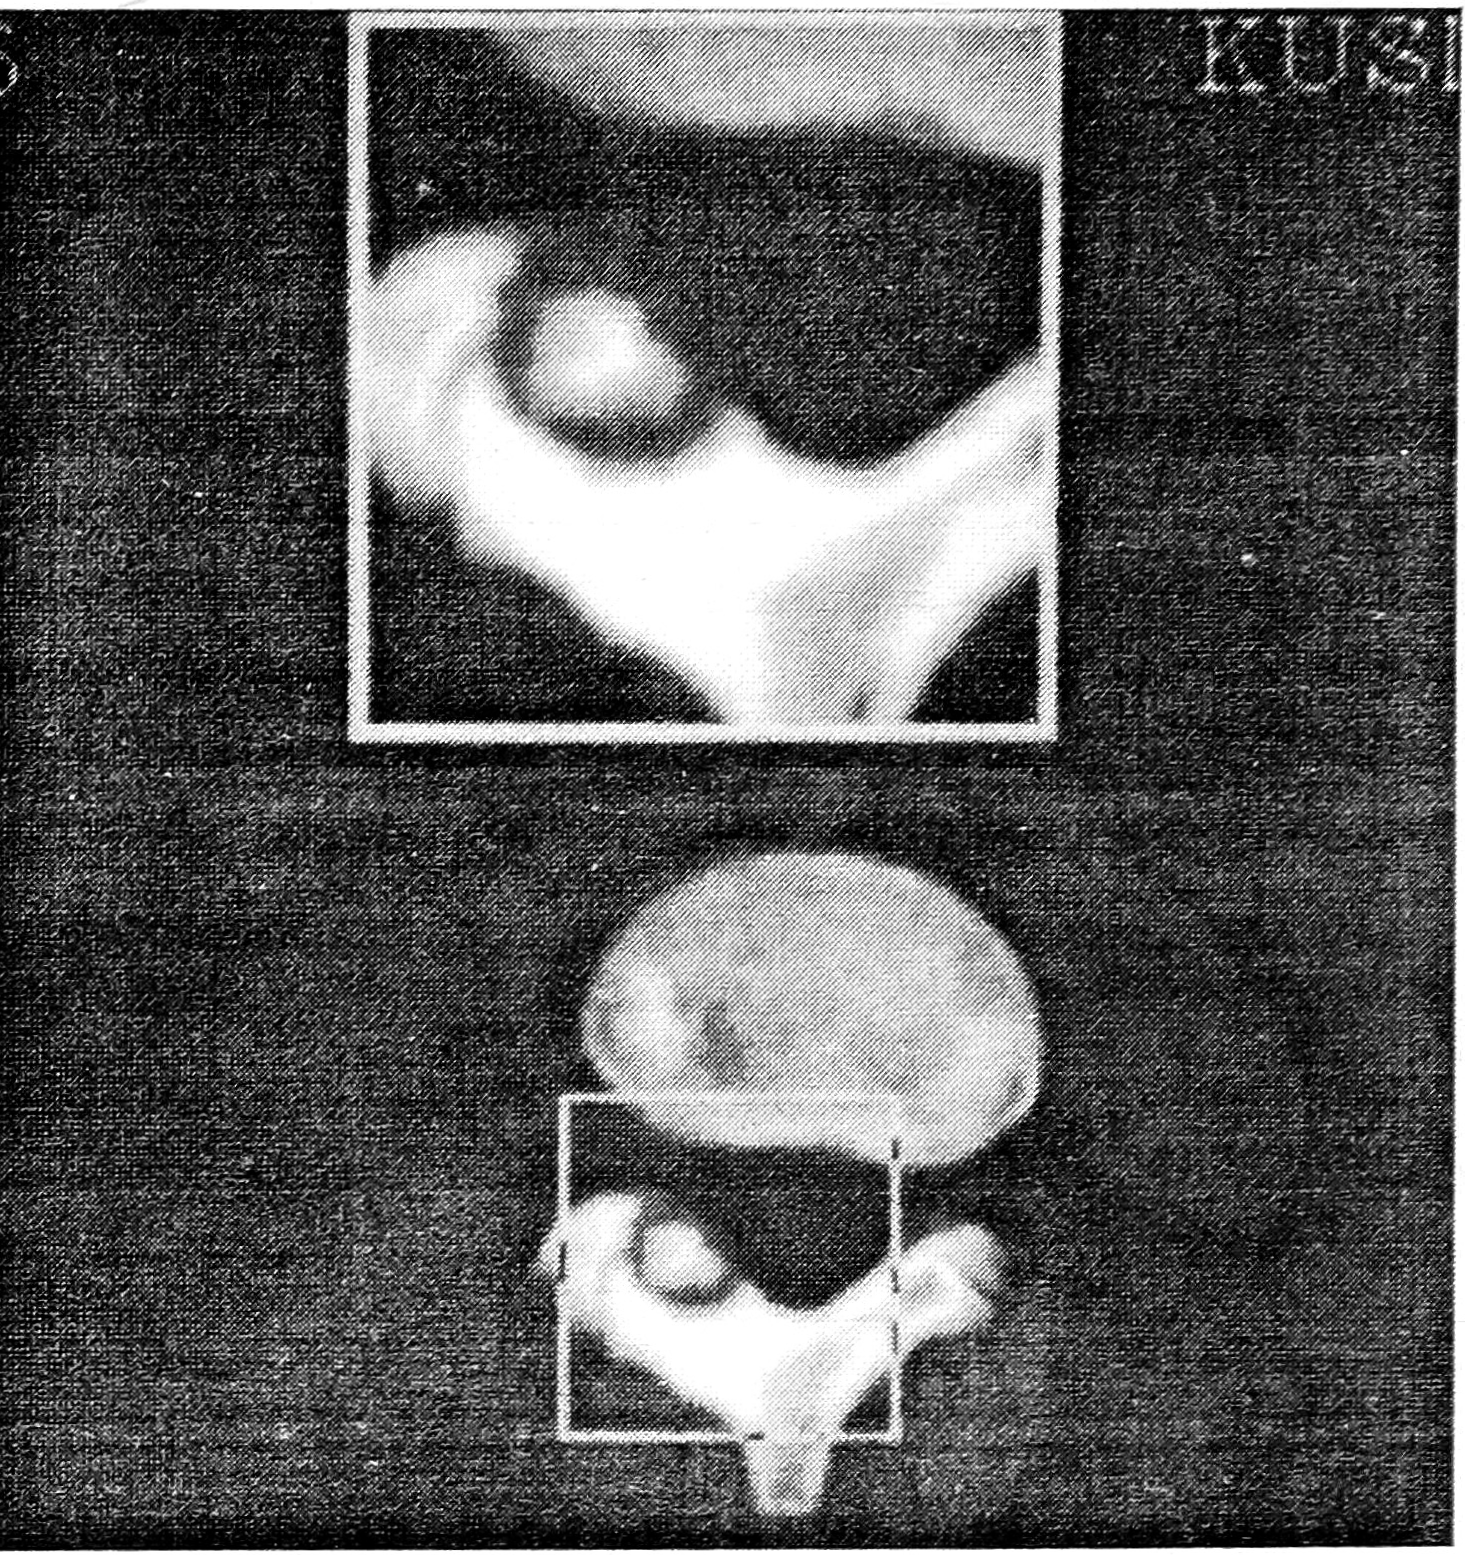

Компьютерная томография в диагностике остеоидной остеомы и остеобластомы занимает ведущее место благодаря ее высокой разрешающей способности и возможности мультипланарной реконструкции изображения. Послойное сканирование позволяет получить объемное изображение очага и достоверно определить его размеры и локализацию, что особенно важно при экстрадуральном расположении опухоли. Патогномоничным признаком остеоидной остеомы является так называемое «гнездо», окруженное зоной склероза (рис. 3). Однако при больших размерах очага рентгеносемиотика изменяется, что заставляет расширить диапазон дифференциальной диагностики. В то же время наличие остеолитического очага, «вздутие» коркового слоя, отдельные включения указывают на остеоидную остеому (рис. 4). Опыт свидетельствует, что перечисленные выше симптомы не являются решающими критериями в диагностике остеобластомы. По нашему мнению, диагноз остеобластомы — диагноз морфологический.

Рис. 3. Компьютерная томограмма: «гнездо» остеоидной остеомы дуги позвонка.

Рис. 4. Компьютерная томограмма: интраканально расположенный очаг деструкции смешанного характера с наличием включений.